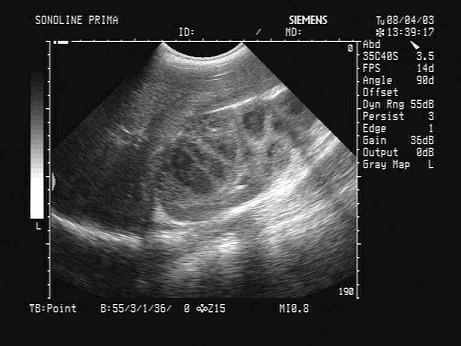

问题 某患者高热,肾区疼痛,肾脏超声声像图如下,最可能的诊断为?(?)

选项 A.肾囊肿 B.急性肾炎 C.脓肾 D.肾癌 E.肾结核

答案 C